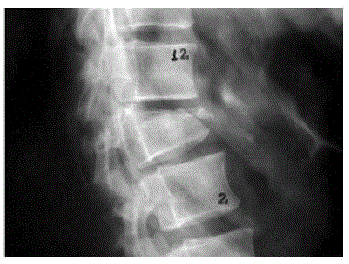

Paciente feminina, 65 anos, vem à consulta com queixa de dor lombar de forte intensidade, de início súbito, há 1 semana que relaciona ao esforço que fez para levantar um vaso grande em casa. Antecedentes de HAS, doença do refluxo gastroesofágico grave, 2 episódios prévios de trombose venosa profunda e insuficiência renal crônica em tratamento conservador (Clearance de creatinina = 26mL/min/1,73m2). Imagem de radiografia de coluna feita no dia anterior à consulta: